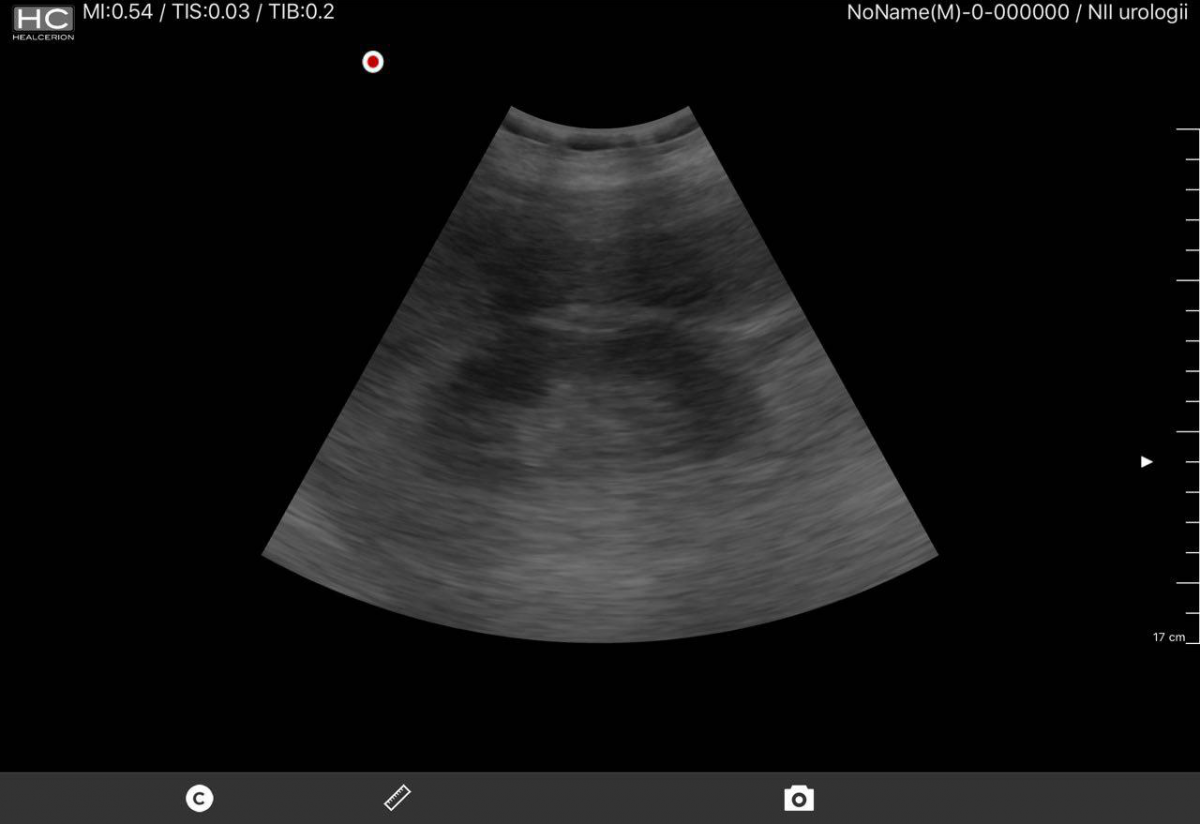

Ниже небольшая галерея скриншотов (почка, мочевой пузырь)

Качество изображения удовлетворительное, оно конечно же несколько не дотягивает субъективно до стационарных аппаратов экспертного класса, но посоревноваться с прочими переносными аппаратами еще как может. Датчик при всей его портативности все же не легкий, уже появляются аналоги чуть ли не в два раза легче. Очень раздражает постоянный шум вентилятора.